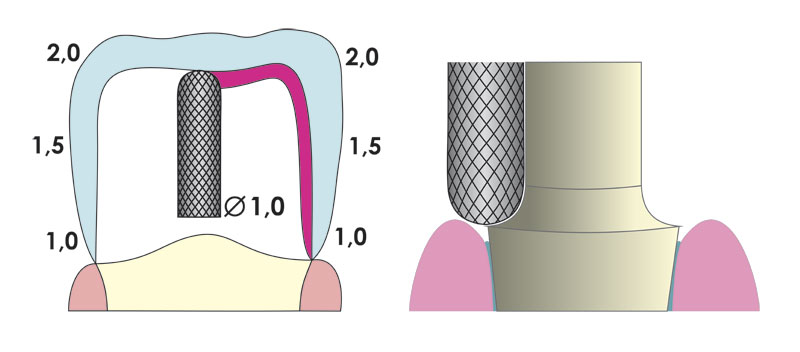

Fogorvosi előkészítés cirkon koronához

Az előkészítés során vállas preparálást ajánlunk 1,5-2,0 mm szélességben, de legalább 1,0 mm legyen mindenhol.